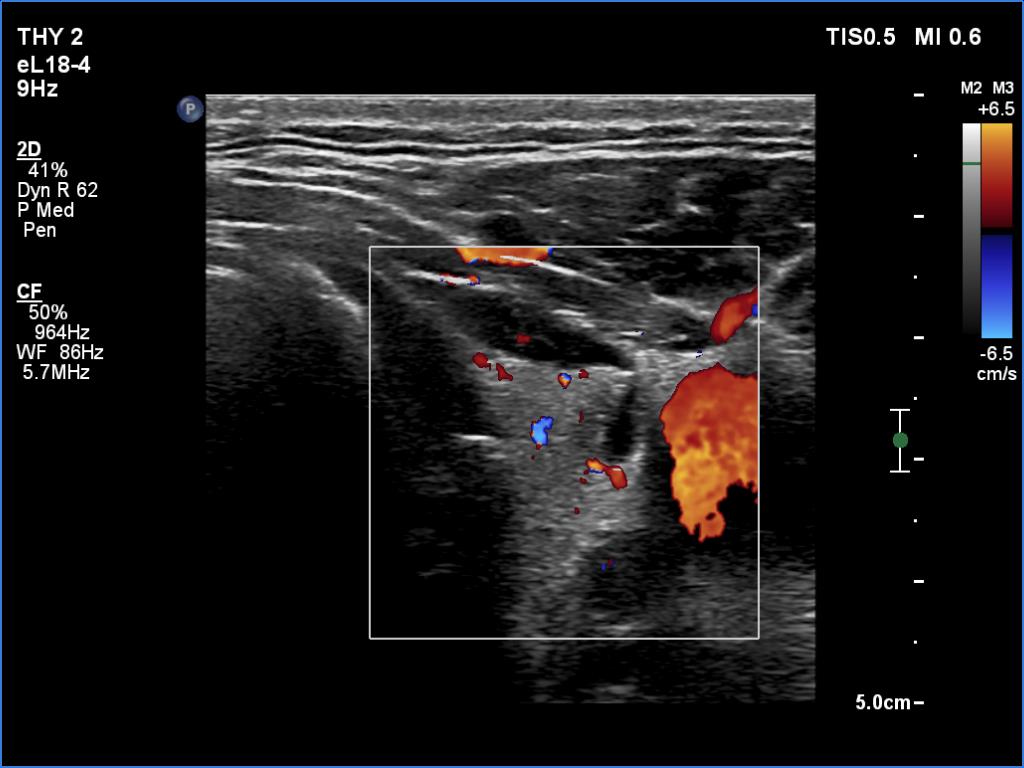

Left lobe, transverse scan, color Doppler mode. The vascularity is not specific.